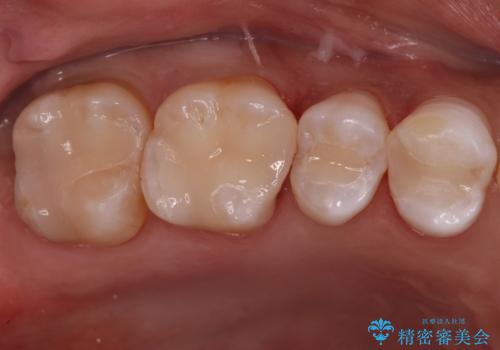

銀が目立つので白くしたい

担当医 青山卓弘

【オールセラミッククラウン】銀歯の下に大きな虫歯

担当医 河野豊嘉